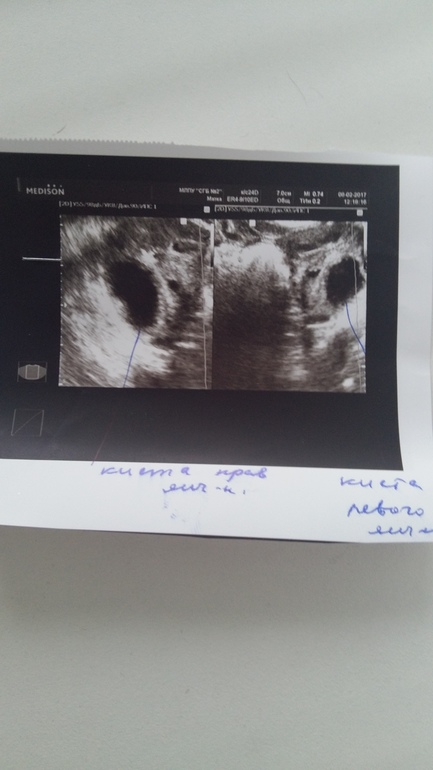

ФолликулометрияМой цикл 28 дней! В прошлом цикле была на УЗИ на 22 дц фолликулы множ.антральные, заключение: признаки поликистоза яичн. Продолжаю пить свои травочки(геникологический сбор) в этом месяце тест на О положительный на 13дц! Через 2 дня -8го февраля полетела я радостная на УЗИ, говорю последние М. Были 24-го янв! Хорошо! Она пишет 10-й дц и говорит что кисты в яичниках(( 22мм-в правом, и 19мм-в левом. Жидкость-небольшое кол-во!

Кисты - это образования, размером более 30 мм. Если же день цикла 10, то можно предположить, что один из этих "кист" все же может быть доминантным фолликулом, хотя, если честно, по фото не особо похожи, левый точно нет.